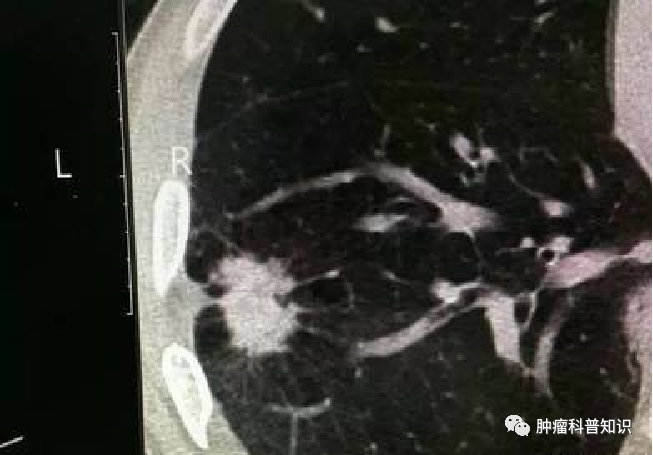

浸润腺癌(IAC)

是微浸润性腺癌的进一步发展,当微浸润性腺癌没有得到及时的治疗,癌细胞就会继续发展,就变成了浸润癌。浸润癌分为早期和晚期,早期浸润癌没有出现远处扩散和转移,可以通过手术进行根除。晚期浸润腺癌出现了癌细胞局部扩散,只依靠手术治疗回天乏术,还需要同时进行放化疗。